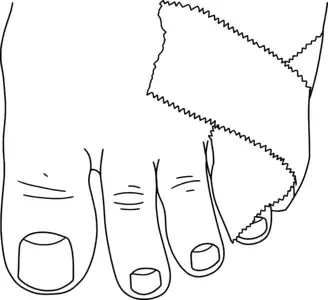

Nonoperative

Fractures of the smaller toes are commonly treated by buddy taping (see image). Padding is used between the toes to keep the space dry[3] and the toes aligned comfortably. If the toes are less comfortable when buddy-taped, the buddy tape should be removed.[5] Stiff-soled shoes that protect the toe from bending are also helpful.[3] Fractures with less than 2mm displacement and less than 25% of the area of the joint surface on the broken part are generally also be treated with buddy taping and stiff shoes; the evidence on this treatment is not extensive.[6]